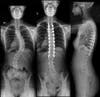

Image shows before and after Isabella’s scoliosis surgery

Despite the brace, her condition was not improving. Not only did Isabella have back problems as a result of adolescent idiopathic scoliosis, but it was affecting her ribs and internal organs. Carolina says it progressed so much that her spine looked like an S.

“We are so appreciative that Dr. Bazzi was able to treat Isabella as well as the nurses and staff at the Children’s Hospital of Michigan. The scar looks perfect, like an artist! Isabella is back to playing tennis and nobody would now know that she had scoliosis. She now has the confidence to wear clothes and cut her hair shorter since she does not have to hide the curvature she had in her spine. For any others considering the surgery, I would highly recommend it. The difference before surgery and after is dramatic and we are so grateful she is back to enjoying life,” says Carolina.